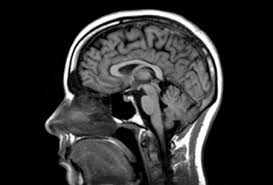

자기공명영상(MRI) 검사는 현대 의학에서 중요한 진단 도구 중 하나로, 강력한 자기장과 고주파 중 라디오파를 이용해 인체 내부의 상세한 이미지를 만들어내는 방법입니다. X-ray나 CT와 달리 방사선을 사용하지 않기 때문에, 반복적인 검사가 필요한 환자에게 특히 유용합니다. 또한, 연부조직에 대한 대조도와 해상도가 우수하여 뇌, 관절, 척추와 같은 부분의 병변을 정밀하게 확인할 수 있다는 장점이 있습니다.

자기공명영상(MRI) 검사의 원리는 핵자기공명(NMR) 원리를 응용한 것으로, 수소 원자의 자기적 특성을 이용해 인체의 다양한 조직을 시각적으로 재현하는 데 사용됩니다. 인체의 70% 가까이가 수소를 포함한 물로 구성되어 있다는 사실에서 출발하며, 수소 원자 내의 원자핵, 즉 양성자가 MRI 검사의 중심에 있습니다. MRI 스캐너는 강력한 자석으로 구성되어 있으며, 이 자석은 적용되는 전자기장 내에서 양성자들을 일정한 방향으로 정렬시키는 기능을 합니다. 양성자들은 외부 자기장에 의해 정렬되었다가, 고주파 전자기 파동이 적용될 때 일시적으로 이 정렬이 방해받게 됩니다. 고주파 신호가 꺼지면 양성자들이 다시 자기장에 정렬되며 이 과정에서 에너지를 방출하게 되는데, 이 에너지가 바로 MRI를 통해 이미지화 하는 데 필요한 신호입니다. 각 조직의 수소 원자핵은 주변 환경의 특성에 따라 다른 패턴으로 에너지를 방출하므로, 이 신호를 분석함으로써 각 조직을 구별할 수 있습니다. 스캐너는 이 신호들을 수집하여 디지털 정보로 전환하고, 컴퓨터는 이 정보를 사용해 인체 조직의 상세한 영상으로 변환합니다.

자기공명영상(MRI) 검사는 특히 연부조직의 구분이 중요할 때 매우 유용한데, 고해상도로 근육, 인대, 뇌와 같은 조직의 시각화를 가능하게 하며, 병변이나 이상을 파악하는 데 도움을 줍니다. MRI는 다양한 방향에서 영상을 얻을 수 있어, 특정 방향으로만 이미지 취득이 가능한 CT나 X-ray보다 더 유연하다는 장점도 가지고 있습니다. 또한, 조영제를 사용하지 않고도 혈관의 영상을 얻을 수 있으며, MRI를 통한 혈관 영상은 동맥류나 혈전과 같은 질병 진단에도 유용합니다.